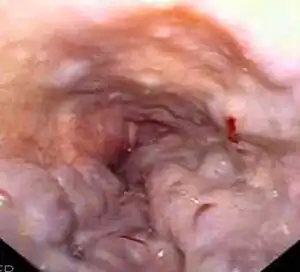

A transjugular intrahepatic portosystemic shunt (TIPS) involves the decompression of the high pressures in the portal circulation by placing a small stent between a portal and hepatic vein. This is done through radiologically guided catheters which are passed into the hepatic vein either through the internal jugular vein or the femoral vein. Theoretically, a decrease in portal pressures is thought to reverse the hemodynamic phenomena that ultimately lead to the development of hepatorenal syndrome. TIPS has been shown to improve kidney function in patients with hepatorenal syndrome.[8][38][39] Complications of TIPS for treatment of HRS include the worsening of hepatic encephalopathy (as the procedure involves the forced creation of a porto-systemic shunt, effectively bypassing the ability of the liver to clear toxins), inability to achieve adequate reduction in portal pressure, and bleeding.[8][38]